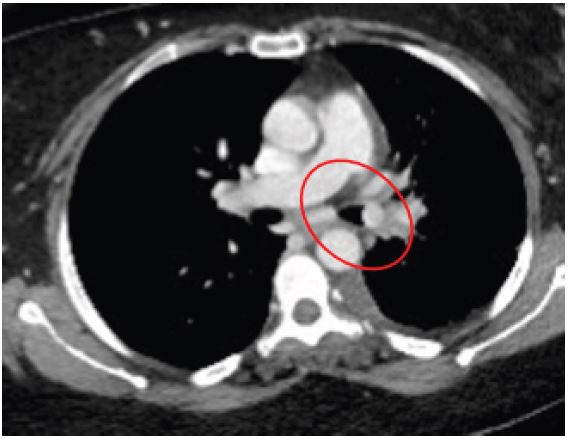

A 42-year-old male presented to our outpatient clinic with a 2-month history of persistent dry cough, mild exertional dyspnea, and occasional wheezing. He was a non-smoker with past history of Bronchial Asthma which was diagnosed 3 years back and patient was on Inhaled salbutamol on as needed basis. Clinical auscultation revealed a localized wheeze over the right lower lobe. Chest X-ray showed a suspicious opacity. CT chest revealed a well-defined lesion at the origin of the right lower lobe bronchus. Bronchoscopy visualized an endobronchial mass, and biopsy confirmed a typical carcinoid tumor.

Figure 2: CT axial image showing endobronchial lesion.